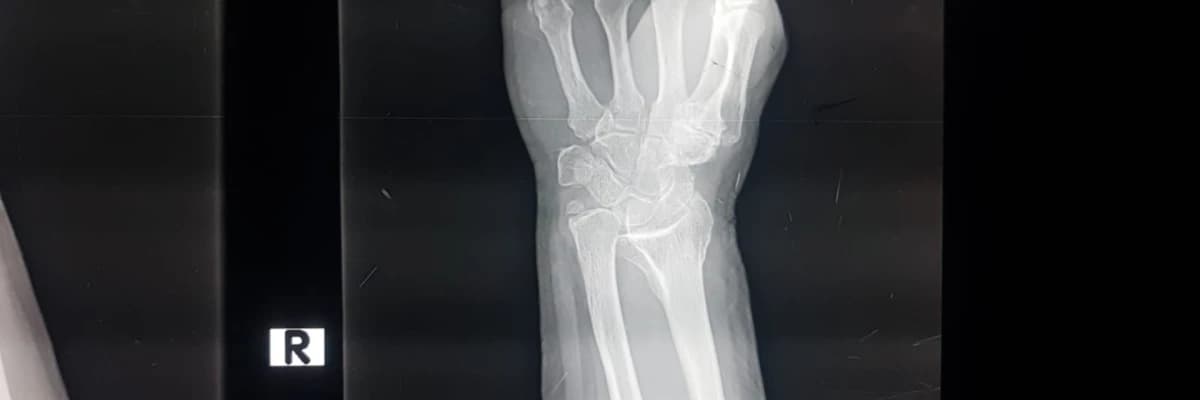

EL BİLEK BÖLGESİ KIRIKLARI

Bu bölge kırıkları genellikle dirsek tam açık ve el bileği geriye açılanmışken avuç içine düşme ile oluşur. Yüklenmenin ve oluşan enerjinin derecesine, yönüne ve yayılımına göre kırığın yeri ve şekli değişir; aktarılan enerjiye ve düşme şekline göre basit bir kırık veya eklem içine ulaşan parçalı, karmaşık ve zor kırıklara kadar olan geniş bir yelpaze gösterebilir. Ayrıca, beraberinde damar,sinir ve yumuşak doku yaralanmaları ve el bileğin diğer kemiklerinin kırıklarıda bulunabilir

Hasta acil servise el bilekte ağrı,şişme ve sekil bozukluğu ile gelir. Ağrı genellikle dayanılmazdır ve ağrı kesicilerle kontrol edilebilir . Hastanın muayenesi ve ardından film çekilerek teşhis konulur.